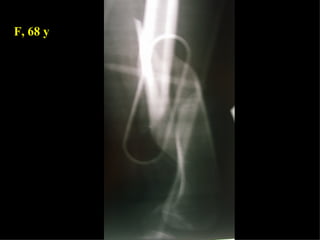

F, 68 y

LISS  NCB

NCB